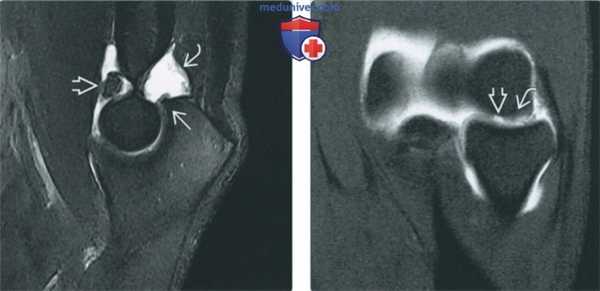

МРТ-артрограмма при хрящевых и костно-хрящевых повреждениях локтевого сустава

(Слева) МР-артрография в режиме PD FS, сагиттальный срез: визуализируются последствия коано-хрящевого повреждения - свободное тело в переднем отделе сустава, остеофит и синовит.

(Справа) МР-артрография в режиме Т1ВИ, коронарный срез: в головке мыщелка плечевой кости отмечается локальный глубокий дефект хряща. Прилежащий отдел хряща имеет неровный контур. Пациент молодого возраста занимался бейсболом.

о Затек контрастного препарата по контуру фрагмента 4. МРТ:

• МР-артрографические признаки в достаточной мере коррелируют со стадиями, выделенными в модифицированной классификации Берндта и Харти

• Стадия I: дефект хряща или наличие в нем зоны патологического сигнала, отек костного мозга

• Стадия II: чашеобразная линия перелома под хрящом (хрящ может восстановиться), отслаивание отсутствует

• Стадия III: отслаивание костно-хрящевого фрагмента, затек под него контрастного препарата

• Стадия IV: костный дефект в месте перелома; смещенный фрагмент может не визуализироваться:

о Контрастный препарат затекает в область дефекта не всегда

о Дефект может быть заполнен фиброзным хрящом

• Стадия V (иногда называется НА): резорбция костной ткани в области костно-хрящевого дефекта:

о Кистозоподобная зона гипоинтенсивного сигнала на Т1 ВИ, гиперинтенсивного на Т2 ВИ и в режиме STIR

о При внутривенном введении контрастного препарата «киста» может накапливать контрастный препарат, если содержит фибринозный субстрат

о При артрографии заполнение «кисты» контрастом отсутствует

(Слева) МР-артрография в режиме Т2ВИ FSE FS, сагиттальный срез: визуализируются «целующиеся» ушибы передней поверхности головки лучевой кости и задней поверхности головки мыщелка плечевой кости, обусловленные перенесенным ранее задним вывихом головки лучевой кости. В этом случае отличить травматический дефект головки мыщелка плечевой кости от псевдодефекта позволяет наличие отека костного мозга.

(Справа) МР-артрография в режиме Т2ВИ FSE FS, коронарный срез, этот же пациент: отмечаются дефект хряща, импрессия субхондрального отдела кости и перифокальный отек костного мозга.